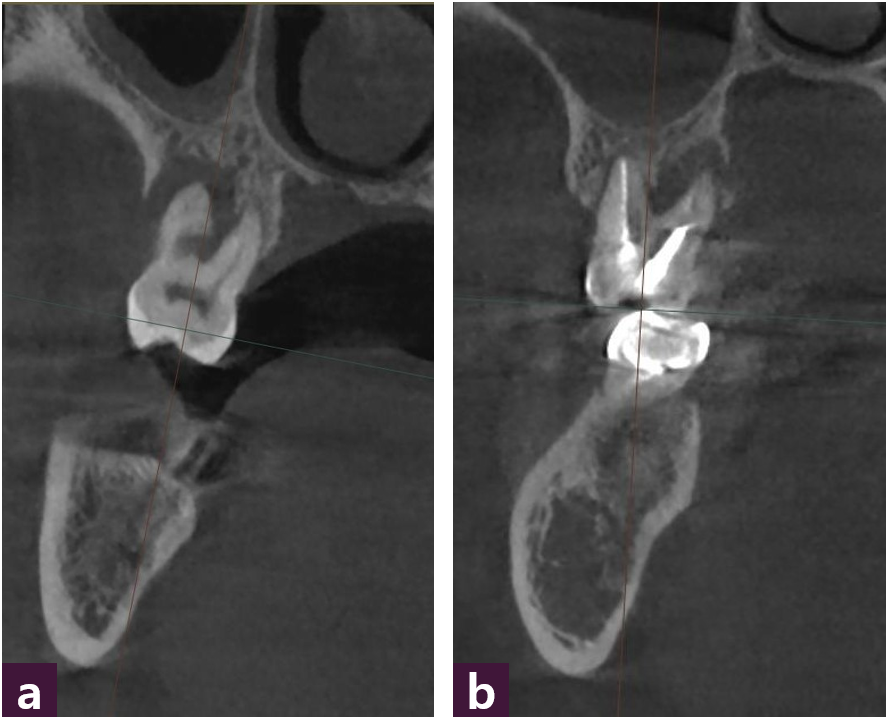

먼저 자료들의 정합을 위하여 결손부 치은 및 안정된 유지가 가능한 치아 특정 부위 3군데에 레진을 부착한다. CBCT에서 전치부에서는 sagittal view, 구치부에서는 coronal view를 우선적으로 파악하며, 동시에 apex부분의 axial view에서 골 파괴 양상과 범위를 꼭 확인하여야 한다. Intraoral photo에서는 교합면의 교합점이 반드 시 표현되어야 하며, 폐구시 buccal overjet를 관찰할 수 있어야 한다. IOS scan에서는 왜곡이 없는 범위내에서 최대한 넓게 획득하며, 레 진 랜드마크 등이 잘 표현되어야 한다 [그림 1].

다음으로는, 교합 외상 요인을 고려하는 과정에서는 결손 형태에 따른 분류가 선행되어야 한다. 예를 들어 구치부 상실이 예상되는 경우, 단층촬영 coronal section에서 협측 골 소실이 치우친 경우 와 설측 골 소실이 치우친 경우로 양분할 수 있다. 또한 근심측이 무너진 경우와 원심측이 무너진 경우 등으로 세분된다. 결손이 치우친 방향에 따라 다음과 같이 4가지 분류를 할 수 있다 [그림 3].